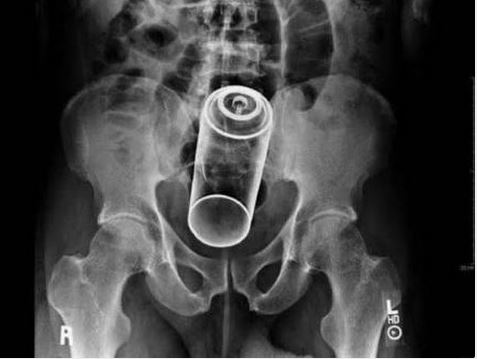

Doktorların görüp yok artık bu nasıl mümkün olur dedikleri röntgen filmleri..

Doktorluğun zor bir meslek olduğu malum. Üstelik bu mesleğin icra ederken bazı zamanlar öyle vakalar ortaya çıkmış ki, doktorlar bile anlamlandırmakta zorluk çekmişler.